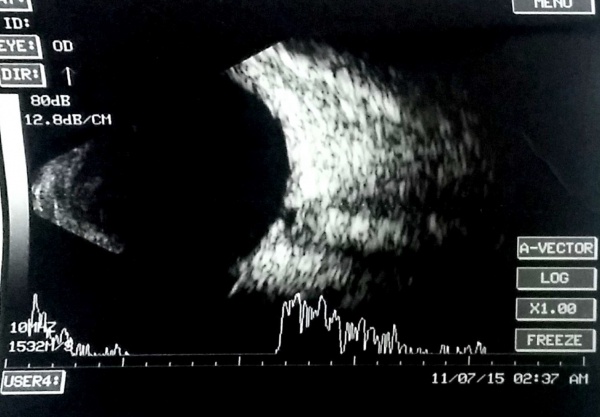

Ultrasonographic appearance of Retinoblastoma

Ocular echogram showing moderate to high amplitude echoes usually with acoustic shadow (calcification) in a child with leukocoria denotes a retinoblastoma unless proven otherwise.